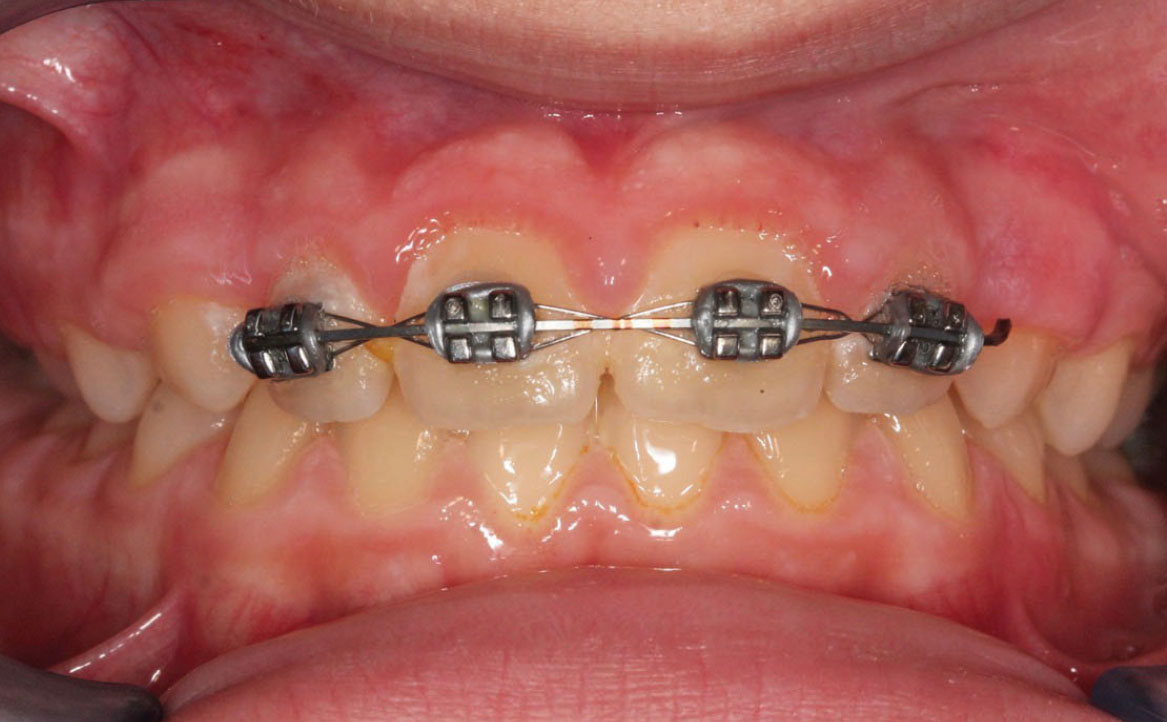

Fig. 4A Foto intraorale in massima intercuspidazione.

A livello intraorale sul piano sagittale è osservabile I classe molare destra e sinistra e classe canina non valutabile per mancanza degli elementi dentari durante la fase di permuta.

L’overjet e l’overbite sono entrambi ridotti in massima intercuspidazione. Trasversalmente il mascellare superiore è contratto (fig. 4-7).